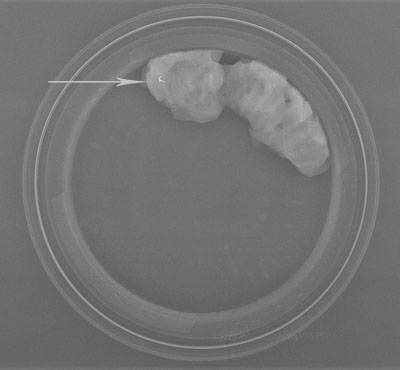

Clip post-biopsies Vérification per-opératoire du clip dans la tumorectomie (le clip est présent dans la pièce opératoire)

Contrôle radiologique de micro-calcifications dans les prélèvements réalisés par macrobiopsies sous stéréotaxie